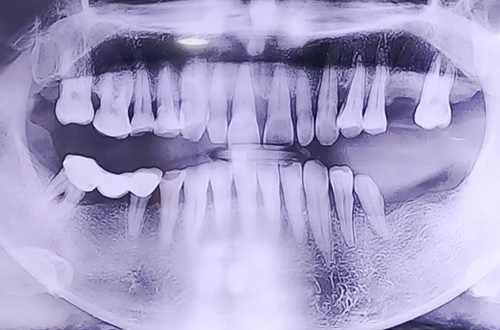

위/아래 어금니 임플란트

BEFORE

왼쪽 위, 아래 어금니가 거의 없어서 오른쪽 치아로만 식사를 하셔야 하는 불편함을 호소하며 내원해 주셨던 환자분이십니다.

발치한 부분의 잇몸 상태나 주변 치아 상태를 꼼꼼히 확인하고 임플란트 식립하였으며, 추가 발치나 뼈이식이 필요한 부분에도 조치를 시행해 드렸습니다.

약 4개월 정도 임플란트가 단단히 자리 잡힌 뒤 예쁘게 보철을 씌워드릴 때 다음 진료일지로 뵙겠습니다! ^^